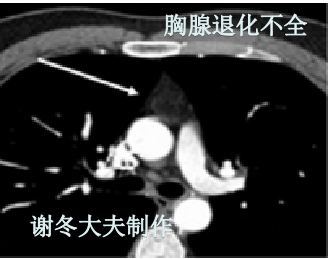

胸腺退化不全是什么意思,ct表现,跟胸腺残留,胸腺增生或胸腺瘤有什么

前纵隔结节胸腺退化不全是什么ct表现跟胸腺残留胸腺增生或胸腺瘤有